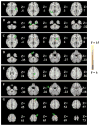

Results: Seven networks revealed abnormalities (five-level one-way ANCOVA, family-wise error correction p < .05): A) fronto-occipital, B) midbrain/cerebellum, C) frontal/thalamic/basal ganglia, D) meso/paralimbic, E) posterior default mode network, F) fronto-temporal/paralimbic and G) sensorimotor networks. Abnormalities in networks B and F were unique to schizophrenia probands. Furthermore, abnormalities in networks D and E were common to both patient groups. Finally, networks A, C, and G showed abnormalities shared by probands and their relative groups. Negative correlation with Positive and Negative Syndrome Scale negative and positive scores were found in regions within network C and F respectively, and positive correlation with Positive and Negative Syndrome Scale negative scores was found in regions in network D among schizophrenia probands only.